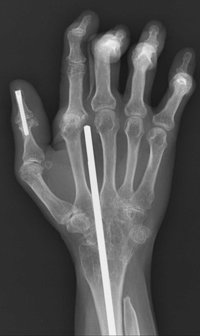

関節を固定する手術は、関節を構成する骨同士をくっつけることで関節を動かなくして、関節の動きに伴う痛みを取り除く方法です。主に手関節(手首)や写真で示した手指の関節、そして足関節(足首)に対して行われます。また脊椎においては、関節リウマチに伴う不安定頚椎(けいつい)に対して固定術が行われることがあります。